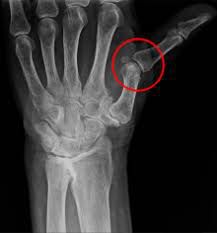

A joint subluxation is a partial dislocation of a joint. It is often the result of acute injury or repetitive motion injury but can also be caused by medical conditions that undermine the integrity of ligaments. The treatment for subluxations may include resetting the joint, pain relief, rehabilitation therapy, and, in severe cases, surgery.